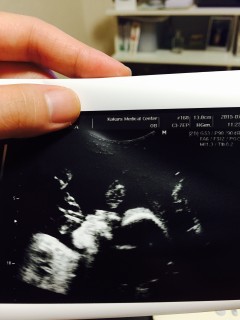

顔をしっかり見られました。下のエコーは右手らしいです。 778gでちょうど平均くらい。